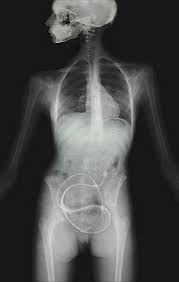

La lombriz solitaria es un parásito que puede afectar a los seres humanos que comen carne cruda. Al no poder consumir suficientes nutrientes del cuerpo humanos, estas producen anemia y desnutrición.